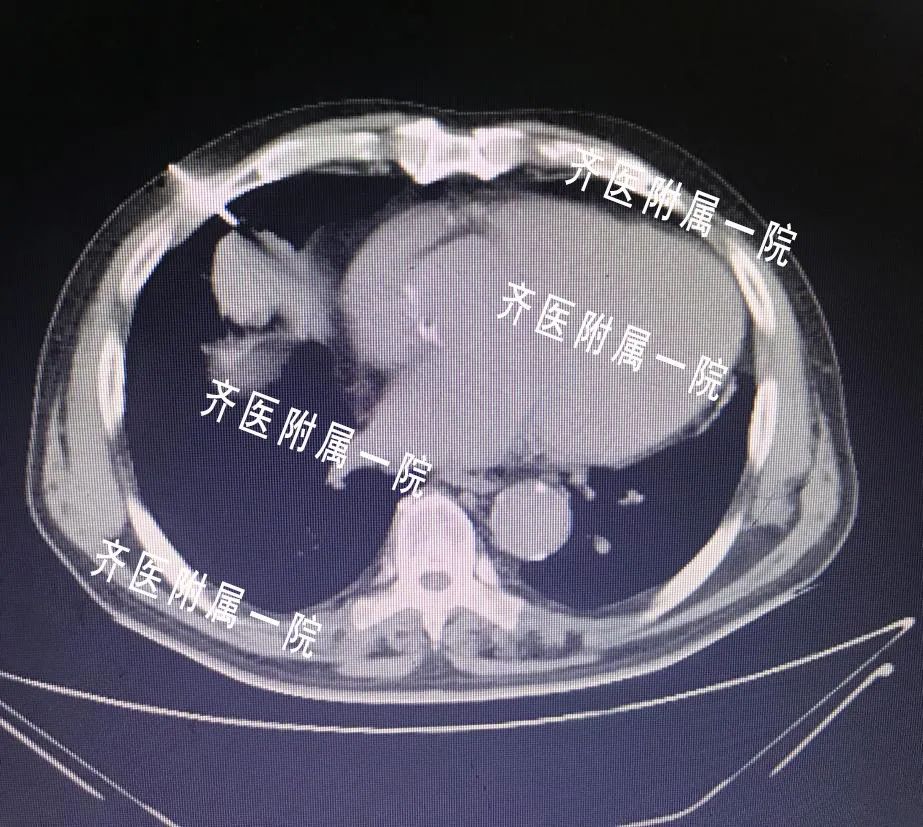

近年来肿瘤的发病年龄越来越年轻化,大家已经开始逐渐重视它。穿刺活检是肿瘤治疗过程中非常重要的一步,肿瘤患者需要选择那些手段治疗,往往有赖于穿刺活检得到的病理结果。首先:看片子做出的诊断叫做“影像学诊断”,只能凭经验初步判断是不是肿瘤,但是具体是哪一种类型的肿瘤,有没有基因突变都不得而知,后面的治疗用药也会盲目。所以,穿刺以后得到的病理结果是医生确诊的金标准,比如下面肿瘤科的这个患者:

此外,同轴活检穿刺无禁区,可以解决因为支气管镜无法解决的问题!